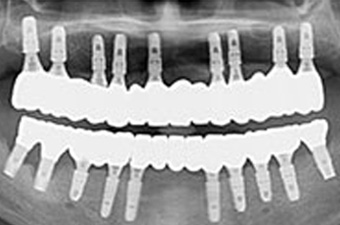

보험 임플란트 치료과정

02

임플란트 식립은 필요 개수만큼 식립 후 여러개의 치아가 하나로 연결된 브릿지 형태 보철물을 필요에 따라 맞춤 제작

03

상악과 마찬가지로 임플란트 식립 후 브릿지 형태로 맞춤 제작해 사용